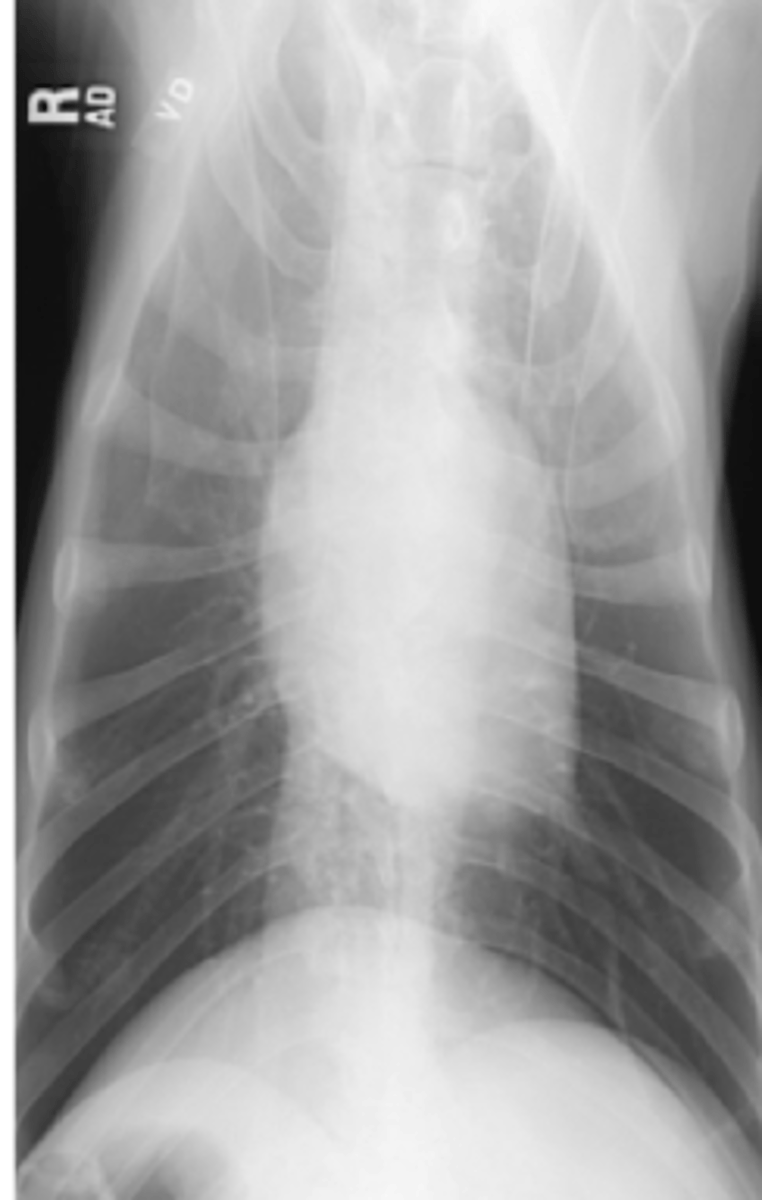

cardiomiopatía dilatada

(perros)

patología:

cardiomiopatía hipertrófica

(gatos)

efusión pericárdica

hernia diafragmática peritoneopericardica